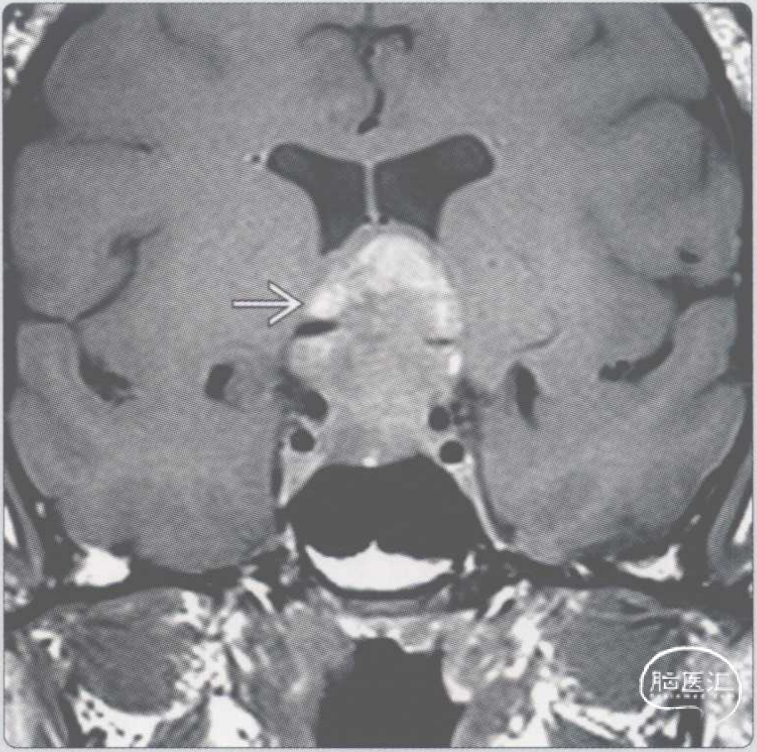

【影像时间·274】一位突发头痛、眼肌麻痹的58岁女性患者